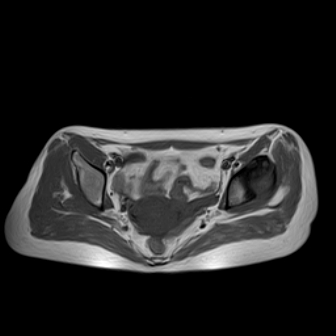

请看看我的片子,我得的什么病,该怎么治疗?谢谢[img][/img]

片子不全,应该是左侧股骨头无菌坏死,右侧似乎没问题,到正规医院治疗,千万别看广告去小医院,吃中药什么的,都是骗人的(说了也白说,百分百都得让人骗点钱才甘心。)

应该是左侧股骨头无菌坏死